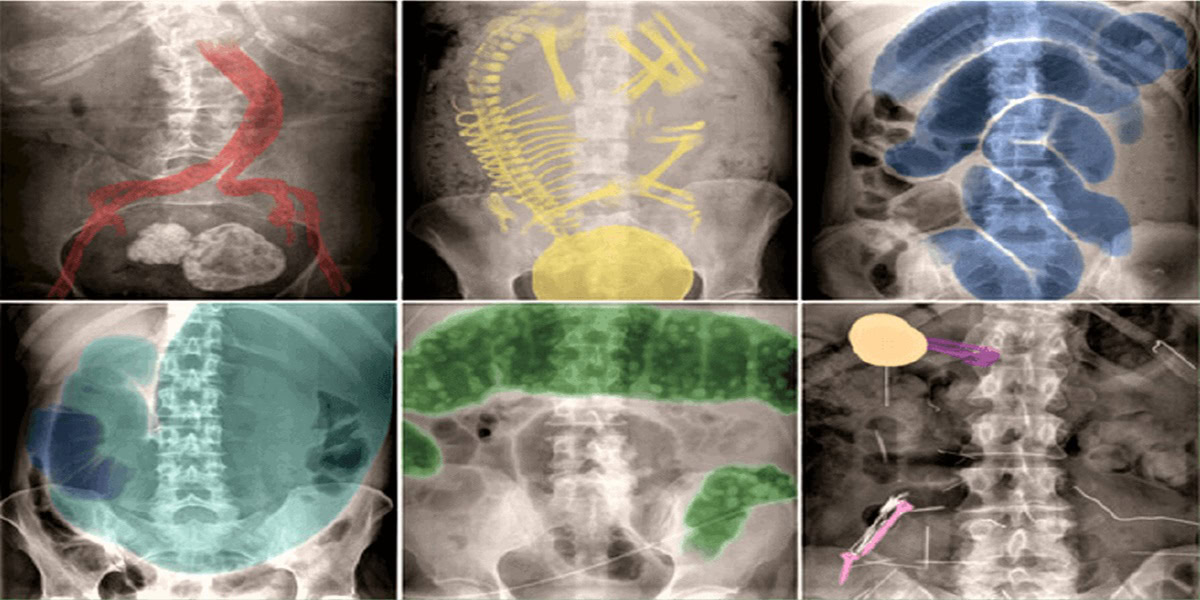

Tại Việt Nam, đau bụng cấp tính chiếm 5-10% nguyên nhân nhập viện cấp cứu. Việc phát hiện nhanh chóng và chính xác các tình trạng khẩn cấp là rất quan trọng để kịp thời điều trị cho người bệnh. Chỉ định chụp XQ bụng ở bệnh nhân đau bụng cấp trên cơ sở đánh giá lâm sàng và xét nghiệm đơn thuần có thể dẫn đến các can thiệp không cần thiết hoặc điều trị chậm trễ các tình trạng khẩn cấp. Ngày nay có nhiều phương tiện chẩn đoán hình ảnh tiên tiến như siêu âm, chụp cắt lớp vi tính và cộng hưởng từ có thể hỗ trợ trong việc ra quyết định lâm sàng, tuy nhiên chụp phim XQ bụng vẫn là một trong những chỉ định được yêu cầu nhiều nhất trong cấp cứu bụng vì giá trị chẩn đoán và tính đơn giản…